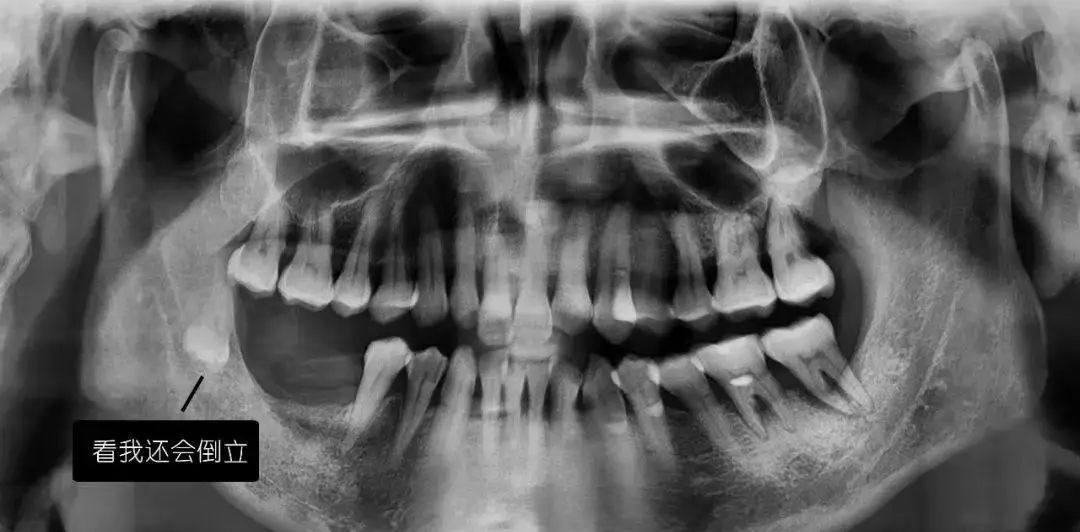

看牙为什么要拍CT?

先放几张图,让你涨涨姿势,

不拍CT根本不知道你的牙齿长得会有多奇葩!